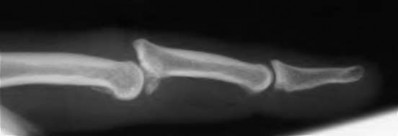

Question 13:

A 40-year-old diabetic male presents with a swollen, painful right index finger after a puncture wound. You suspect pyogenic flexor tenosynovitis. Kanavel's classical cardinal signs for this condition include all of the following EXCEPT:

Correct Answer: Erythema extending proximally into the mid-palm

Explanation:

Kanavel's four cardinal signs of flexor tenosynovitis are: 1) fusiform (sausage-like) swelling of the digit, 2) severe pain with passive extension, 3) a flexed resting posture of the digit, and 4) tenderness along the entire course of the flexor tendon sheath. Erythema extending to the mid-palm is not one of Kanavel's specific signs, though localized erythema may be present.